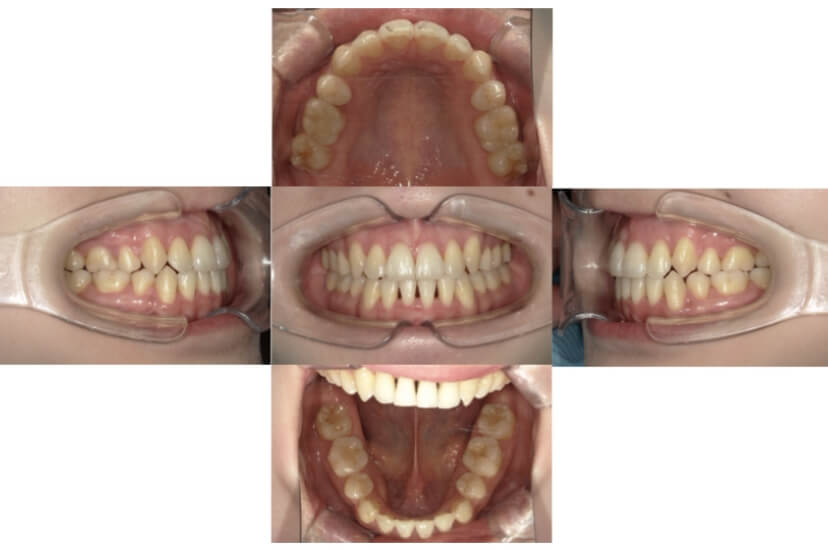

BEFORE

AFTER

症例4

下顎前突、叢生

抜歯

ブラケット矯正

上下顎叢生、反対咬合(上下の前歯のガタガタ、若干受け口)のケースです。

装置はラビアル(上下表側)で、上下顎の小臼歯を4本抜歯を行っています。抜歯したスペースを使って、上下の叢生改善と前歯の受け口の改善を行っています。

主訴 前歯のガタガタを治したい。

年齢・性別 45歳 女性

お住まいの地域 神奈川県川崎市

治療方針 抜歯スペースを利用して上前歯の叢生(ガタガタ)の改善と受け口の改善

抜歯部位 上顎左右第一小臼歯、下顎左右第二小臼歯

使用装置 ラビアル(上下表側)、顎間ゴム

治療期間 2年6か月

治療回数 20回

リテーナー クリアリテーナー